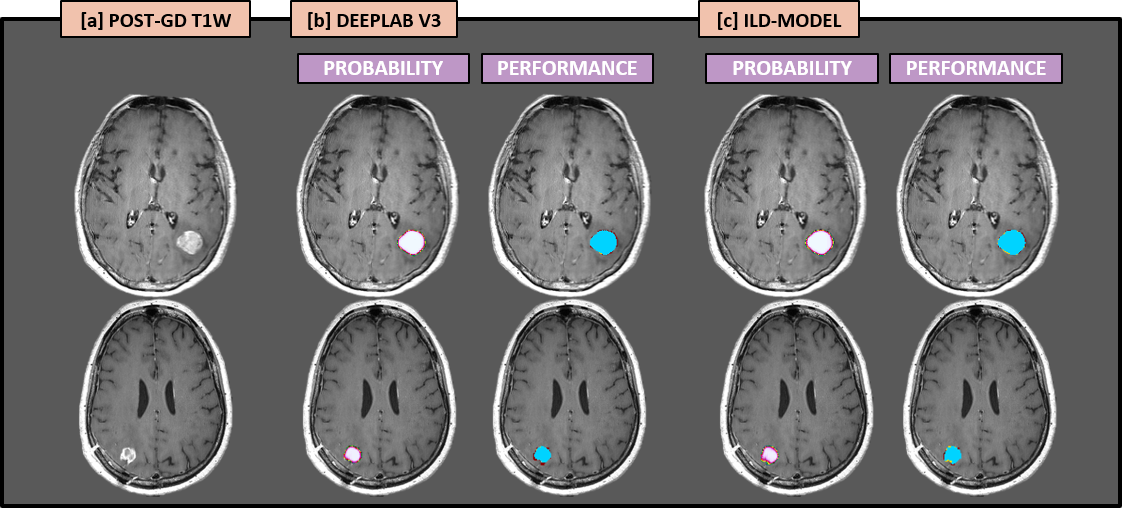

In our paper entitled ‘Handling Missing MRI Sequences in Deep Learning Segmentation of Brain Metastases: A Multi-Center Study’, which is published in npj – Digital Medicine, we aimed to improve the robustness and generalizability of our segmentation network by utilizing an input-level dropout (ILD) model. A diagram showing the ILD-pipeline, as well as four example cases with resulting AI-based segmentations, is shown in Figure 1. In this neural network, a dropout layer at the input-level is trained on the full set of four distinct MRI sequences, as well as every possible subset of the MRI sequences. This way, our ILD-model can allow segmentation even in the setting where individual MRI sequences are missing. This enabled us to generalize our deep learning segmentation model for use in multiple different imaging sites.  Our model showed high performance and accuracy, equivalent to that of expert neuroradiologists, in a separate cohort of patients with different scanners and imaging protocols.

Figure 1: Diagram showing the neural network pipeline used in this study. The left column shows MRI data from four representative example cases. The MRI data is fed into the input-level dropout (ILD) model shown in the middle column. The right column shows the predicted segmentation as likelihood-maps overlayed the input MRI-data. The voxel-wise likelihood of being within a metastatic lesion is indicated by the color-bar.